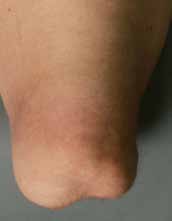

Der direkten postoperativen Nachbehandlung (Abb. 7 u. 8) kommt eine besondere Bedeutung zu. Nach der Amputation kommt es spontan – wie auch beim entspannten Liegen – zu einer Außenrotationslage des Beines. Hierdurch liegt der laterale Femurkondylus dann direkt auf der Bettauflage auf. In der frühen postoperativen Phase kann es leicht zu Drucknekrosen kommen, die das Operationsergebnis zunichtemachen. Oft reibt („shivert“) der Patient mit dem Stumpf in der Aufwachphase auf der Bettoberfläche; teilweise versucht er, sich mit dem Stumpf beim Aufrichten auf dem Bett abzustützen. Daher muss bei der postoperativen Verbandtechnik die Druckreduktion in diesen Bereichen durch Wattewickel garantiert werden (s. Abb. 7); der Operateur muss sich nach der Operation noch am OP-Tag darüber vergewissern.